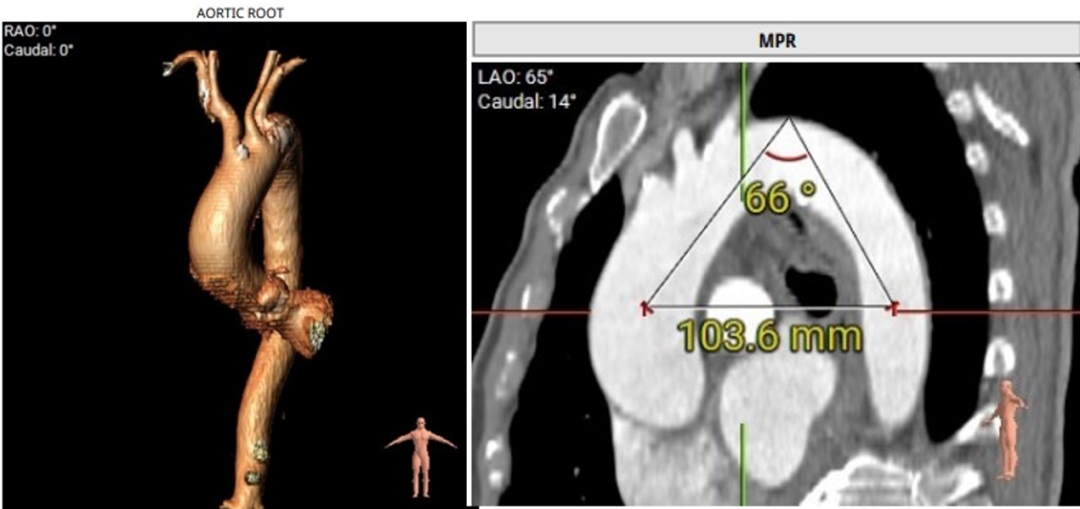

Type 0 型二叶瓣,钙化较重。LCA与RCA起源于同个窦部,高度可。主动脉弓部与根部角度尚可,主动脉弓部钙化团块。下肢入路尚可,右股动脉前壁钙化团块。瓣环26.7mm,LVOT 26.9mm,STJ 32.7mm。

LCA与RCA起源于同个窦部

主动脉弓部与根部角度尚可,主动脉弓部钙化团块